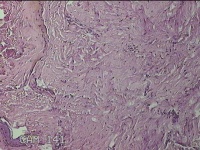

右下腹部切口结节

性别

女

年龄

27岁

临床诊断

皮下结节

一般病史

发现右下腹部切口结节10余年。

标本名称

大体所见

灰白暗红色带皮肤样结节2.3x1.3x0.8cm一个。表面糜烂,切面灰白色,质硬。

需要侵袭性纤维瘤病和纤维瘢痕鉴别一下